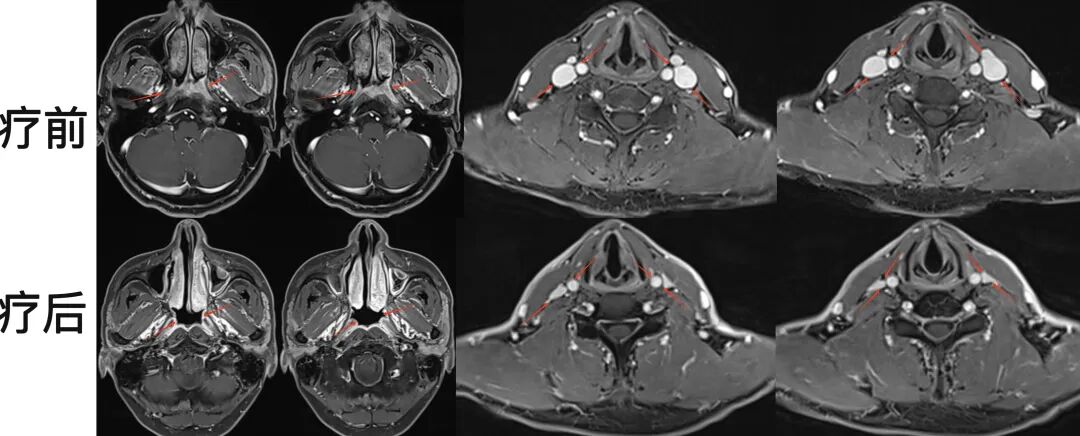

病例1:33歲女性患者,鼻塞、耳悶、涕中帶血為主要癥狀。磁共振檢查可見鼻咽區(qū)腫物侵犯雙側(cè)鼻咽腔,左側(cè)為著,侵犯翼突區(qū),屬于局部晚期鼻咽癌?;颊咧委熀?,病灶完全縮退,癥狀緩解,達(dá)到局部腫瘤的完全控制。

圖注:治療前后比對(duì)。上排為治療前,可見鼻咽病灶累及兩側(cè)腭帆張肌、提肌、左側(cè)翼內(nèi)肌及左側(cè)翼突內(nèi)外側(cè)板;下排為治療后,鼻咽區(qū)腫瘤病灶完全消失。治療過程中患者耐受性良好,未出現(xiàn)嚴(yán)重副反應(yīng)。

病例2:62歲男性患者,耳悶起病。磁共振檢查可見鼻咽區(qū)腫物侵犯雙側(cè)鼻咽腔,左側(cè)病灶向前侵犯翼突區(qū)。